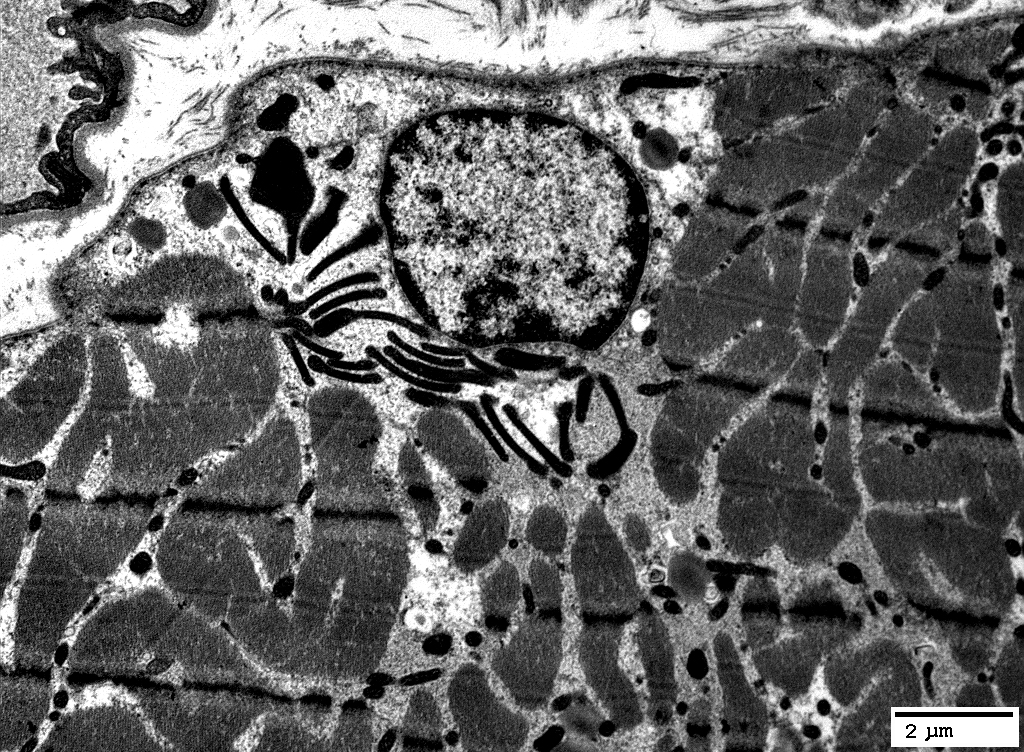

Mitochondria: Subsarcolemmal accumulations

Many mitochondria are abnormal: Large; Long; Dark-stained

From: R Schmidt; C Cai

Many mitochondria in 1 fiber are: Large; Dark-stained

From: R Schmidt